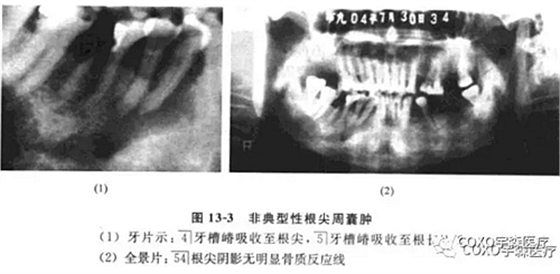

(二)非典型性根尖周囊腫根尖周囊腫的診斷除臨床癥狀外,主要靠X線片檢查。經(jīng)典的診斷標(biāo)準(zhǔn)應(yīng)為在相應(yīng)患牙的根尖部呈現(xiàn)界限清楚的圓形骨質(zhì)稀疏的透射陰影。

周邊可有不同程度白色骨質(zhì)反應(yīng)線;但是不應(yīng)忽略有時根尖部 線區(qū)表現(xiàn)可以呈非典型性。

病例:女性,72歲,右下牙齦腫脹3周,有牙痛史,外院拍片診斷為“根尖周囊腫”并行頰側(cè)組織切片檢查,病理診斷為“炎癥性病變”轉(zhuǎn)來我院。

檢查:54]頰側(cè)骨膨隆,頰側(cè)活檢切口無膿性分泌,54]無松動,無叩痛,6]殘冠、x線片示:654]]冠部均有充填物,4]牙槽骨吸收已近根尖,51]牙槽骨吸收至根長1/2。全景片示:54]根尖陰影,無明顯骨質(zhì)反應(yīng)線(圖13-3),54]電活力測試無反應(yīng)。

局麻下拔除654],見根尖部有大量肉芽組織予以刮除,術(shù)后傷口順利愈合。病理報告:右下后牙區(qū)根尖周囊腫,伴反應(yīng)性骨質(zhì)增生。

分析與評述

本病例的臨床診斷為根尖周囊腫,似無太大疑問,但X線表現(xiàn)則十分不典型:54]根尖骨質(zhì)呈不規(guī)則、潛穴性吸收,底部幾達(dá)顏孔,更無明顯骨質(zhì)反應(yīng)線。由于54]無明顯松動及叩痛,加之頰側(cè)骨質(zhì)膨脹,致使牙體牙髓病醫(yī)師疑為腫瘤,不敢進(jìn)行根管治療術(shù)。手術(shù)結(jié)果證實仍為根尖周囊腫伴反應(yīng)性骨質(zhì)增生。結(jié)合術(shù)中見病灶區(qū)有大量肉芽組織,說明本病例的炎癥過程可能持續(xù)時間較長,程度較重,致使 線片表現(xiàn)呈不典型性。本例的經(jīng)驗是:應(yīng)牢記根尖周囊腫還有不典型表現(xiàn)者,臨床應(yīng)綜合各方面的因素考慮,方能更進(jìn)一步提高臨床診斷水平。